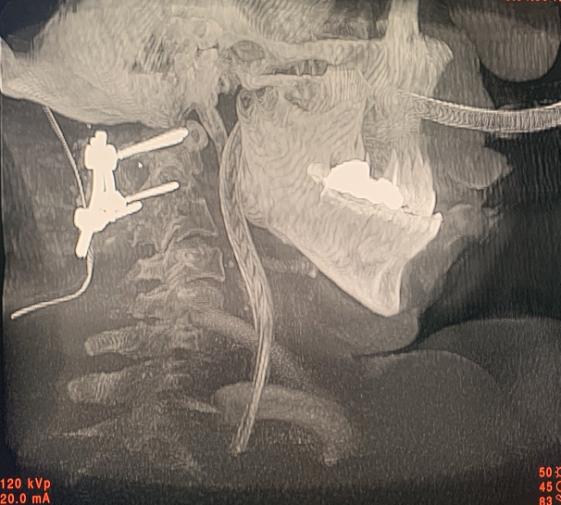

术中取骨融合术后照片

术后颈椎三维CT成像:内固定物位置良好,寰枢椎脱位复位满意